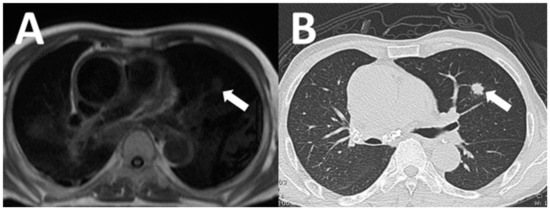

| Lung cancer | 4 (16) |

| Pulmonary thromboembolism | 2 (8) |

| Aortic dissection | 2 (8) |